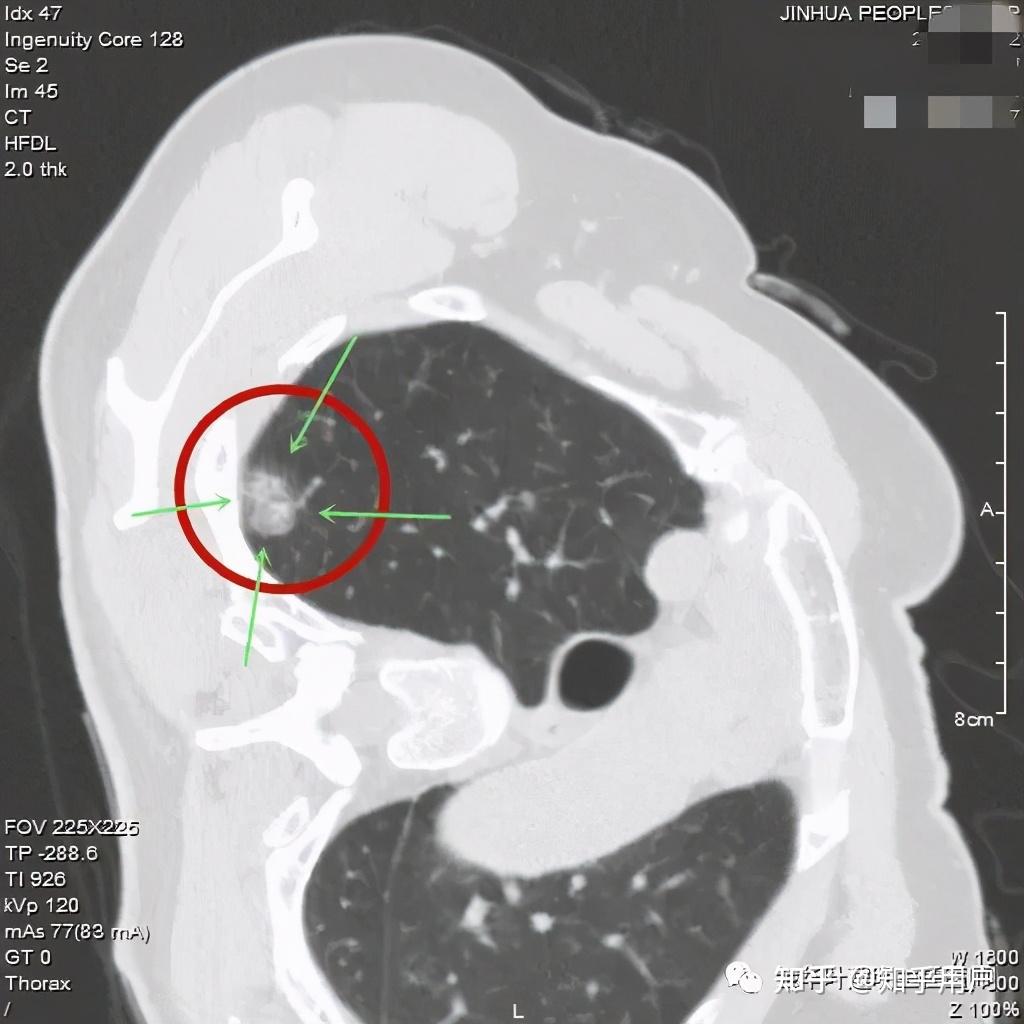

影像上的表现,原位腺癌应该是5-30毫米的纯磨玻璃结节,密度均匀,CT值在-600以下,极少有空泡、毛刺、胸膜牵拉和分叶,可以有血管穿行,但无血管弯曲。当然若病灶在10毫米以上时,诊断原位腺癌要慎重,因为1厘米以上的病理上是原位腺癌的少见。

看着,非常不错,以后原位腺癌与非典型增生不是癌了,不需要手术了,至少不能按恶性肿瘤的方式进行手术了。这是好事!但真的到了临床上,如何把握,我看仍是前路漫漫,迷雾重重!我们先举几个例子,来看看影像上如何来区分AAH、AIS、MIA以及浸润性腺癌。下面的四幅CT图分别各是其中的一种,是我们术后有病理依据确诊的病例,你能分出哪张是哪种吗?

有没有高手能分辨出来?我是一头雾水,根本分不清到底哪个是哪种。都是纯磨玻璃结节,都是瘤肺边界清楚,大小都在1厘米左右或以下。现比如下面这四幅CT图也是分别为AAH、AIS、MIA以及浸润性腺癌(贴壁型),你能分得清楚哪幅图是哪种吗?

这几乎就是四胞胎,长的没什么区别,但病理类型天差地别。现在把AAH与AIS剔除出恶性肿瘤后,更是差别巨大了,是癌与非癌的区别了,但没有手术切除病检的情况下,你如何来区分?